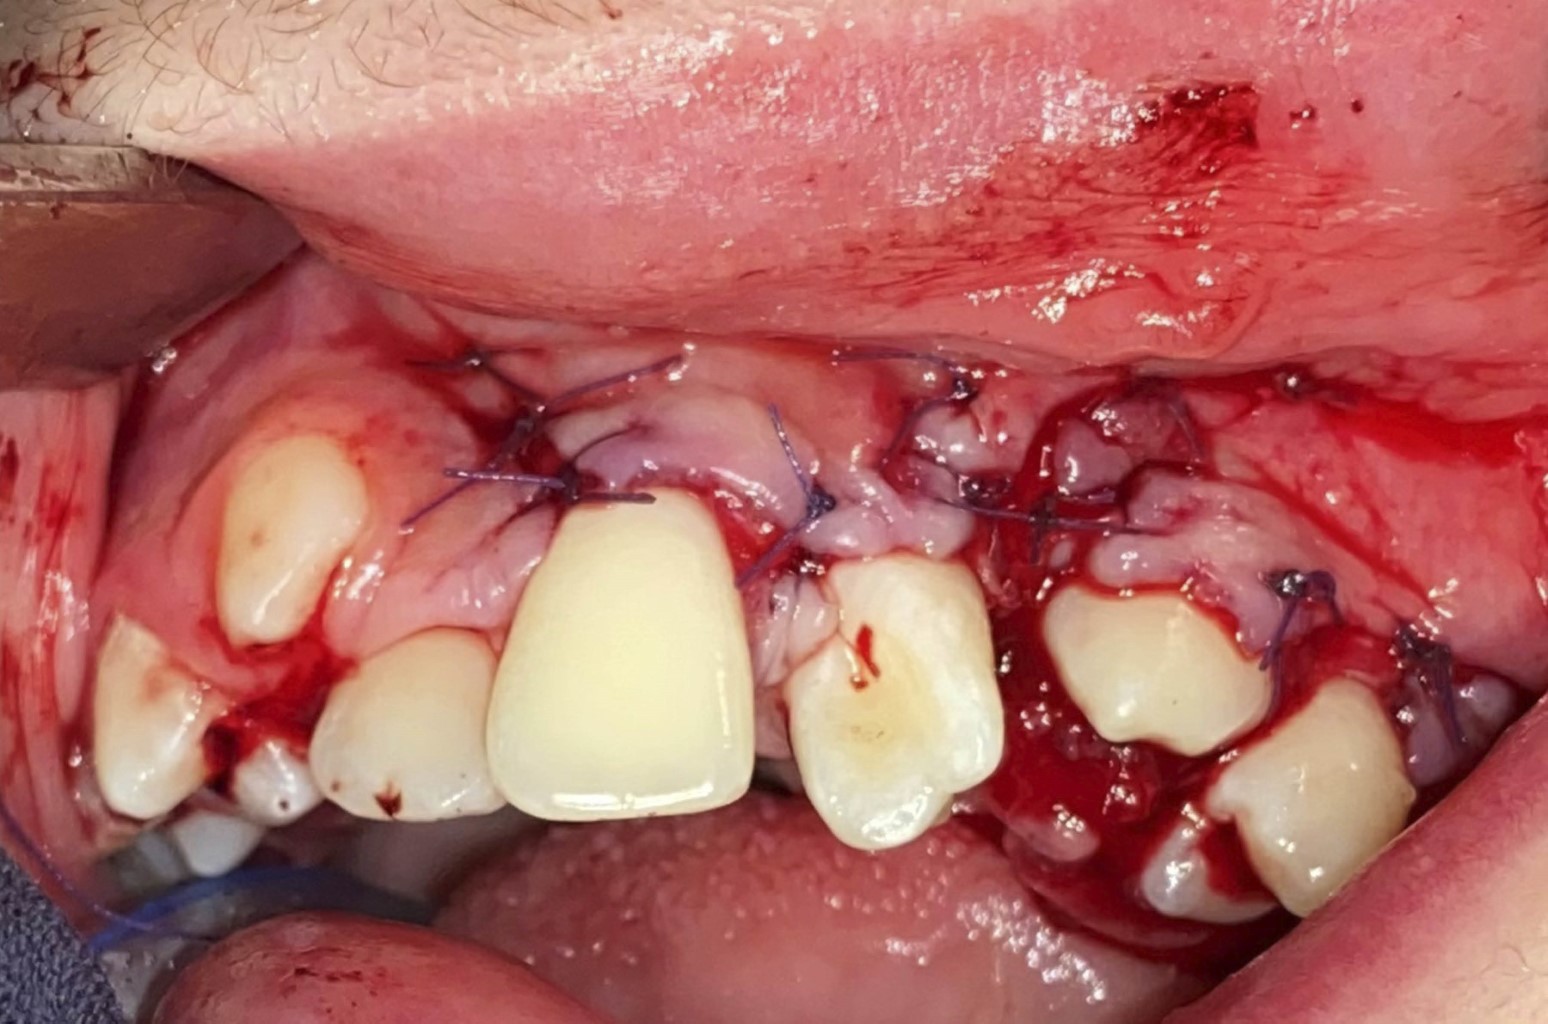

Figure 1

Figure 2

Figure 3

Figure 4

Figure 5

Figure 6

Figure 7